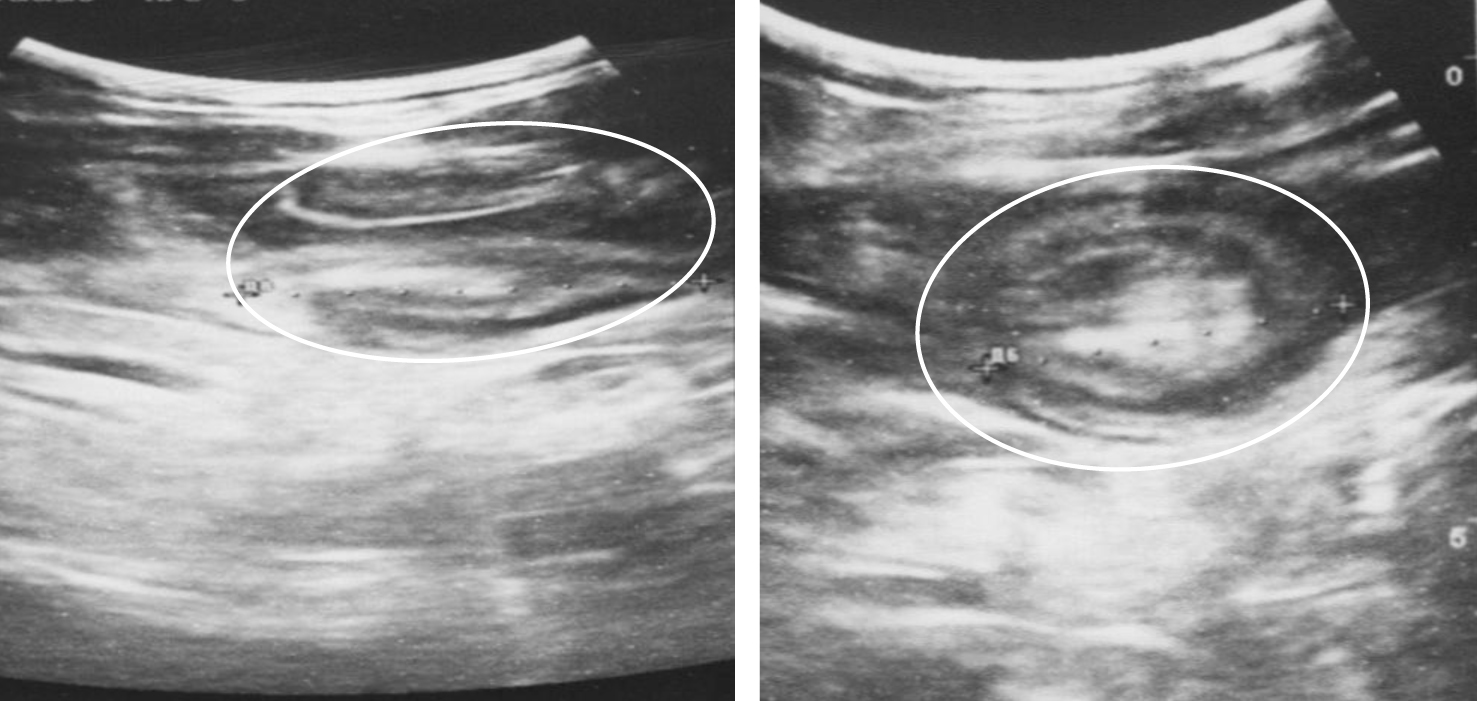

Рис. 3. Ультразвуковая картина инвагинации, инвагинат отмечен белым контуром

Ультразвуковое исследование, выполненное в плановом порядке 17 пациентам с персистирующей ОКН и купированным КК, позволило выявить ОТК только у троих (17,6 %).